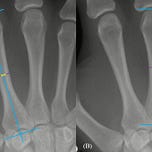

A new longitudinal study1 of adolescents and young adults shows that even after the hormonal storms of puberty have passed, the human skeleton continues to quietly remodel itself. The evidence comes not from dramatic changes in stature or limb length, but from the slow thickening of cortical bone in the metacarpals, the slender bones that form the framework of the hand. These changes extend well into the late teenage years and beyond, challenging assumptions that have shaped biological anthropology, forensic science, and interpretations of the fossil record.